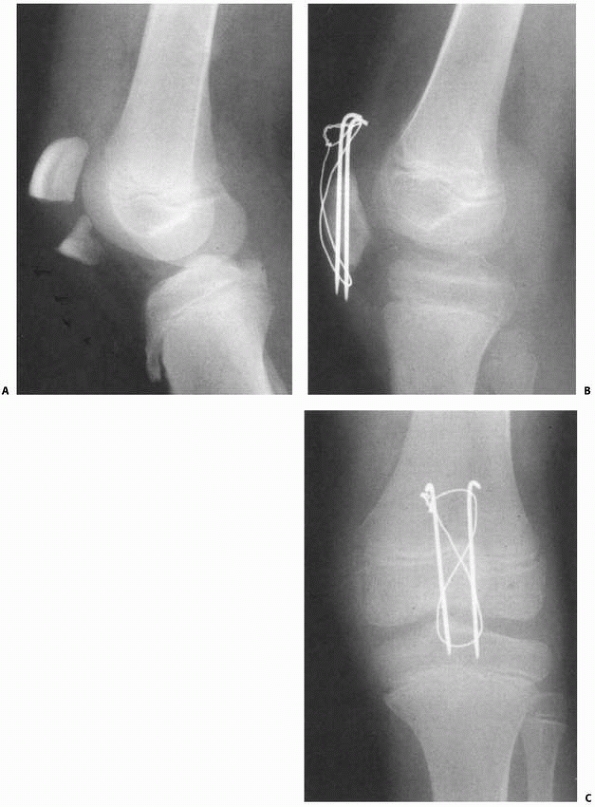

the distal femoral physis, without fracture through the adjacent

epiphysis or metaphysis (Fig. 23-7). It occurs

in infants as a birth injury or abuse and in adolescents, often as a

nondisplaced separation. This type of fracture may go undetected.

![]() |

FIGURE 23-7 A. Salter-Harris type I fracture of the distal femur in an 8-year-old. B. Lateral view shows hyperextension. C. Fixation following closed reduction under general anesthesia. Note that pins are widely separated at the fracture site. D. Lateral view of fixation.

|